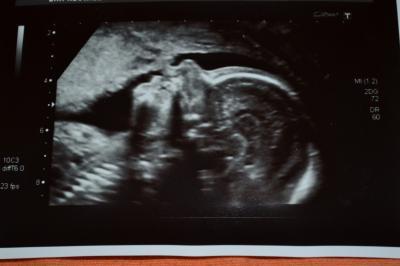

Wenn das nicht meine sind.......

Bild zu